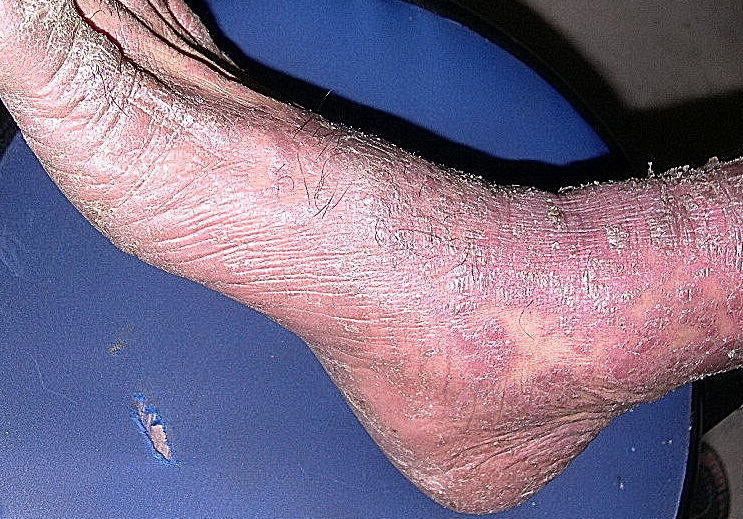

Psoriasis_erythrodermic = الأحمرية الصدفية